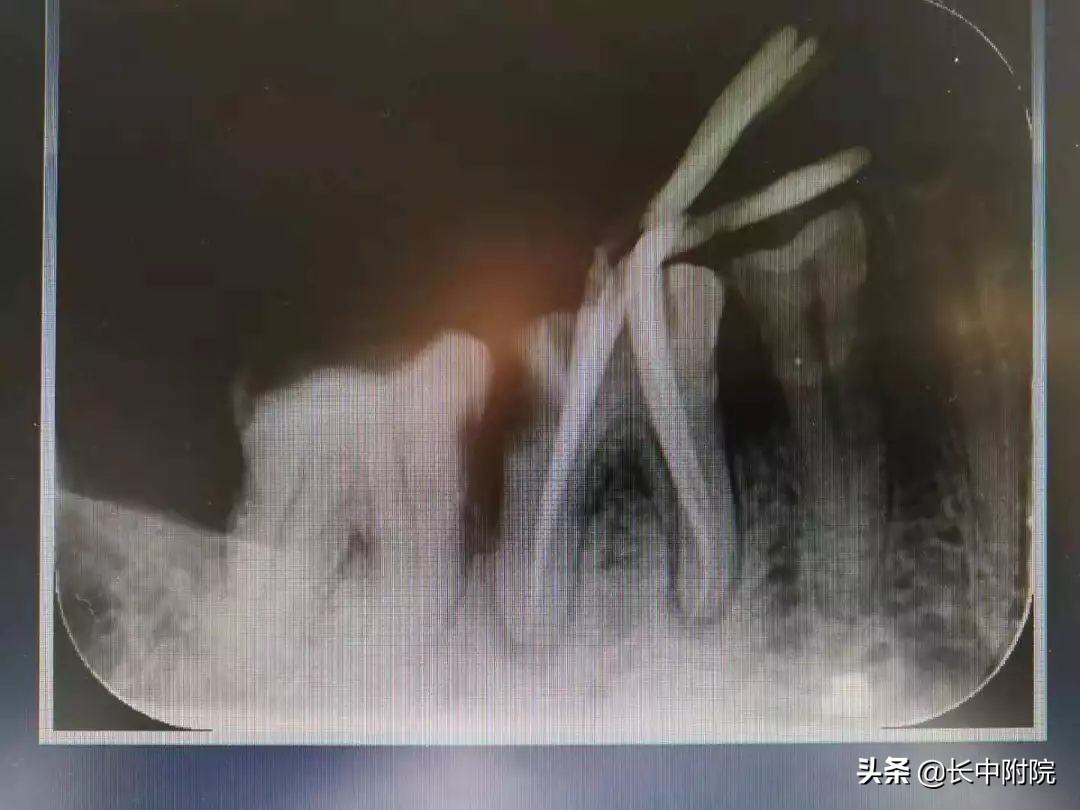

3.确定根管工作长度

应用平行投照X线方法、根管长度测量仪确定根管度,最好插针拍X片。